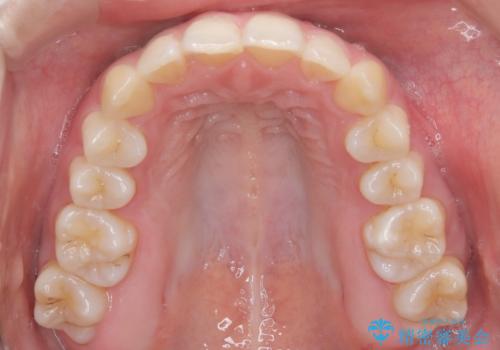

前歯のガタガタと欠損部を改善

- 患者様は、前歯のガタガタ(叢生)と左下5番の欠損部が気になるとのことで来院されました。診断の結果、インビザラインを用いて前歯の叢生を整えながら、左下5番の欠損部にはインプラント治療を計画しました。矯正治療により、歯並びを改善すると同時に、噛み合わせのバランスも向上させることを目標としました。矯正期間とインプラントの治療計画を並行して進めることで、患者様のご希望に応えるプランを立てました。

前歯の叢生改善のため、インビザラインによる透明で目立たない矯正装置を使用しました。治療中は、歯の移動による負担を最小限に抑えつつ、歯列全体のバランスを考慮して進めました。左下5番の欠損部には、矯正終了後にインプラントを埋入し、自然で機能的な咬合を回復しました。治療期間中、患者様には装置の正しい装着と日々の清掃を徹底していただき、歯肉やインプラント周囲の健康を保つようサポートしました。結果として、美しい歯並びと快適な噛み合わせを両立させることができました。